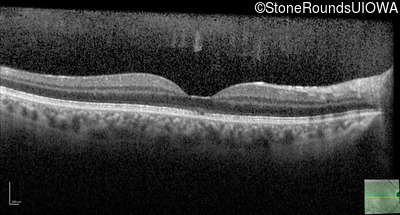

Optical Coherence Tomography - Right - 20/63 +2 sc

Exemplar / OCT Stack

OCT Stack